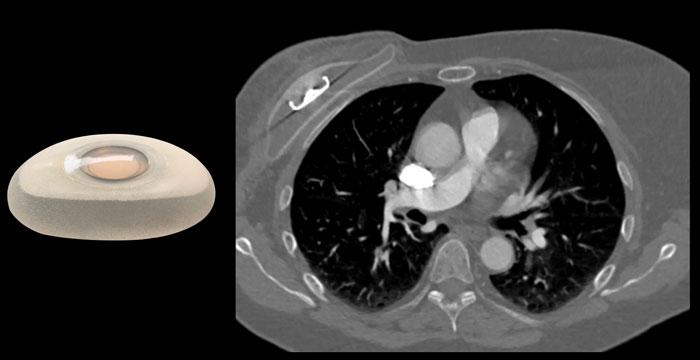

Túi độn ngực bao gồm một lớp vỏ ngoài bằng silicone và phần nhân bên trong được làm từ silicone hoặc nước muối sinh lý.

Túi độn nhân nước muối và túi độn nhân silicone được cắt đôi để thấy phần nhân có hình dạng ổn định bên trong.

Túi độn nhân silicone

Loại túi độn ngực được sử dụng phổ biến nhất bao gồm lớp vỏ ngoài bằng elastomer silicone và phần nhân bên trong là gel silicone.

Phần nhân silicone đã được cải tiến qua nhiều năm để trở thành khối có hình dạng ổn định hơn (xem hình).

Túi độn nhân nước muối

Túi độn nhân nước muối cũng có lớp vỏ ngoài bằng silicone. Chúng có thể được sử dụng chủ yếu để nâng ngực thẩm mỹ hoặc dùng làm túi giãn mô vú trong phẫu thuật tái tạo như một thiết bị tạm thời, được bơm dần bằng nước muối sinh lý. Túi độn nhân nước muối dễ bị xẹp ngay lập tức hơn khi gặp chấn thương.